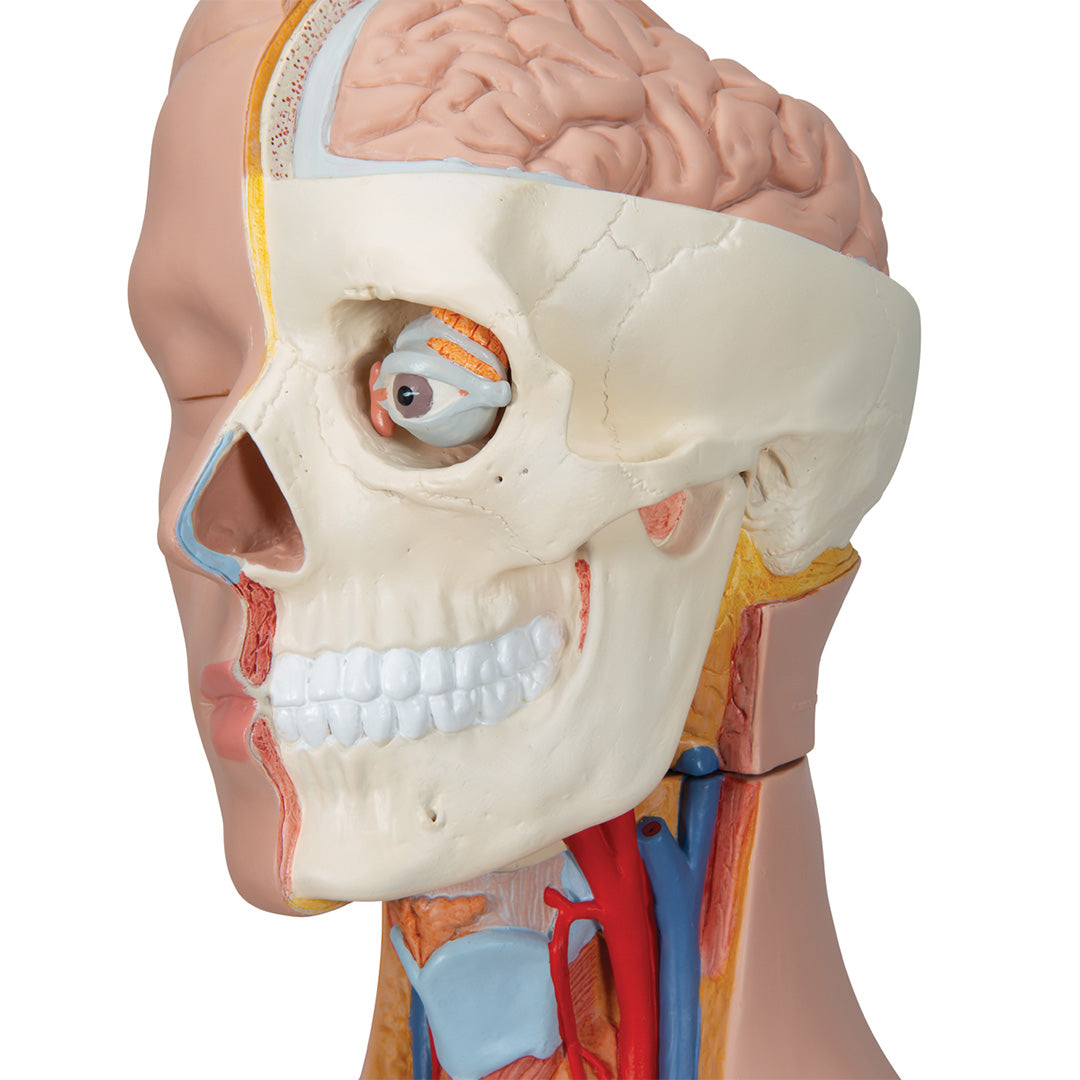

Sobre la anatomía interna humana.

• Cabeza en 2 partes